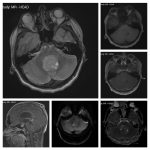

Neurosurgery and neuroradiology always go hand in hand. This little weekly activity is going to enhance the scan reading skills of our audience in an interactive way. Waiting for the answer for a week will keep the curiosity alive and will keep our target audience hooked to the website. It will prove to be a seamless share of knowledge and reading skills.

Dr. Saqib Kamran Bakhshi started the PANS Weekly Image Challenge in 2022, and his creativity and efforts made it a popular activity; engaging trainees and consultants in Pakistan and abroad.